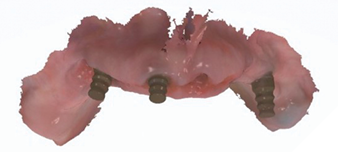

The patient returned 2 weeks from the impressioning appointment for a prototype try in. At this appointment the esthetics, phonetics, soft tissue approximation and occlusion were confirmed. There was no requirement for a verification jig due to the accuracy of the Nexus solution. The restorations were manufactured with milled gold anodized titanium bars overlaid with monolithic zirconia (Figs. 24A-C, 25A-C).

Fig. 24A

Fig. 24B

Fig. 24C

Fig. 25A

Fig. 25B

Fig. 25C